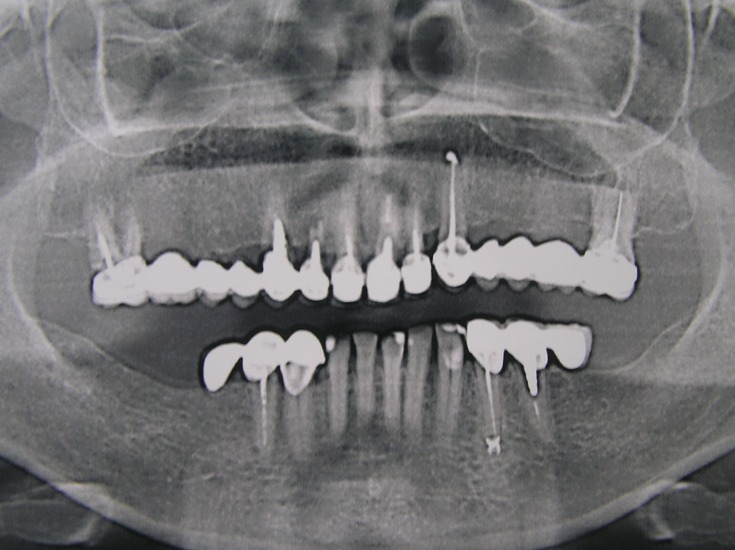

Clinical case: Patient T, 55 years old.

Diagnosis: Combined Maxillary Dentition Defect (Ye. I. Gavrilov).

Treatment: Implantation in the area of 14, 15, 16, 17, 24, 25 and 26 teeth with Alpha Dent Implants.

Fixation of temporary bridge prosthesis, making of metal-ceramic bridge prosthesis.

Result: Complete and total restoration of maxillary dentition aesthetics.

At present the patient’s mandible is being rehabilitated.